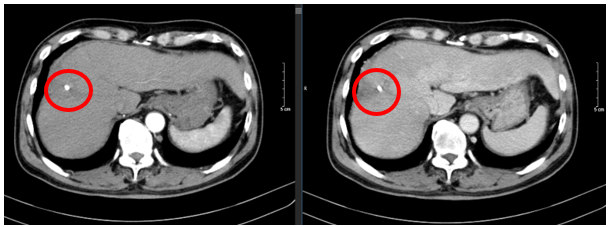

Ngày 26/12/2024: (sau 17 chu kì)

Hình 5: Hình ảnh chụp cắt lớp vi tính ổ bụng: Nhu mô vùng ngoại vi sát bao gan hạ phân thùy VII – VIII có đám (vòng tròn đỏ) giảm tỉ trọng kích thước ~ 21x48mm, trong có lắng đọng vật liệu nút mạch, sau tiêm không ngấm thuốc, không có huyết khối.

Ngày 03/03/2025: (sau 20 chu kì)

Hình 6: Hình ảnh chụp cắt lớp vi tính ổ bụng: Nhu mô vùng ngoại vi sát bao gan hạ phân thùy VII – VIII có đám (vòng tròn đỏ) giảm tỉ trọng kích thước ~ 22x45mm, trong có lắng đọng vật liệu nút mạch, sau tiêm không ngấm thuốc, không có huyết khối.

Nhận xét: Bệnh nhân đạt đáp ứng tốt với điều trị: khối u thu nhỏ kích thước đáng kể sau 20 chu kì (từ 81x51mm xuống 22×45 mm). Đánh giá theo tiêu chuẩn RECIST 1.1, bệnh đáp ứng một phần (PR – Partial Responce).